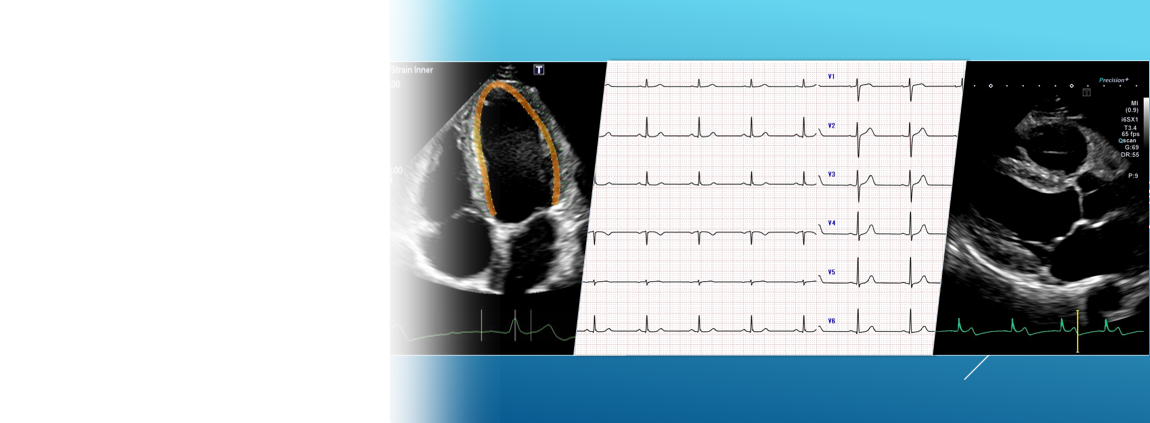

各検査室紹介